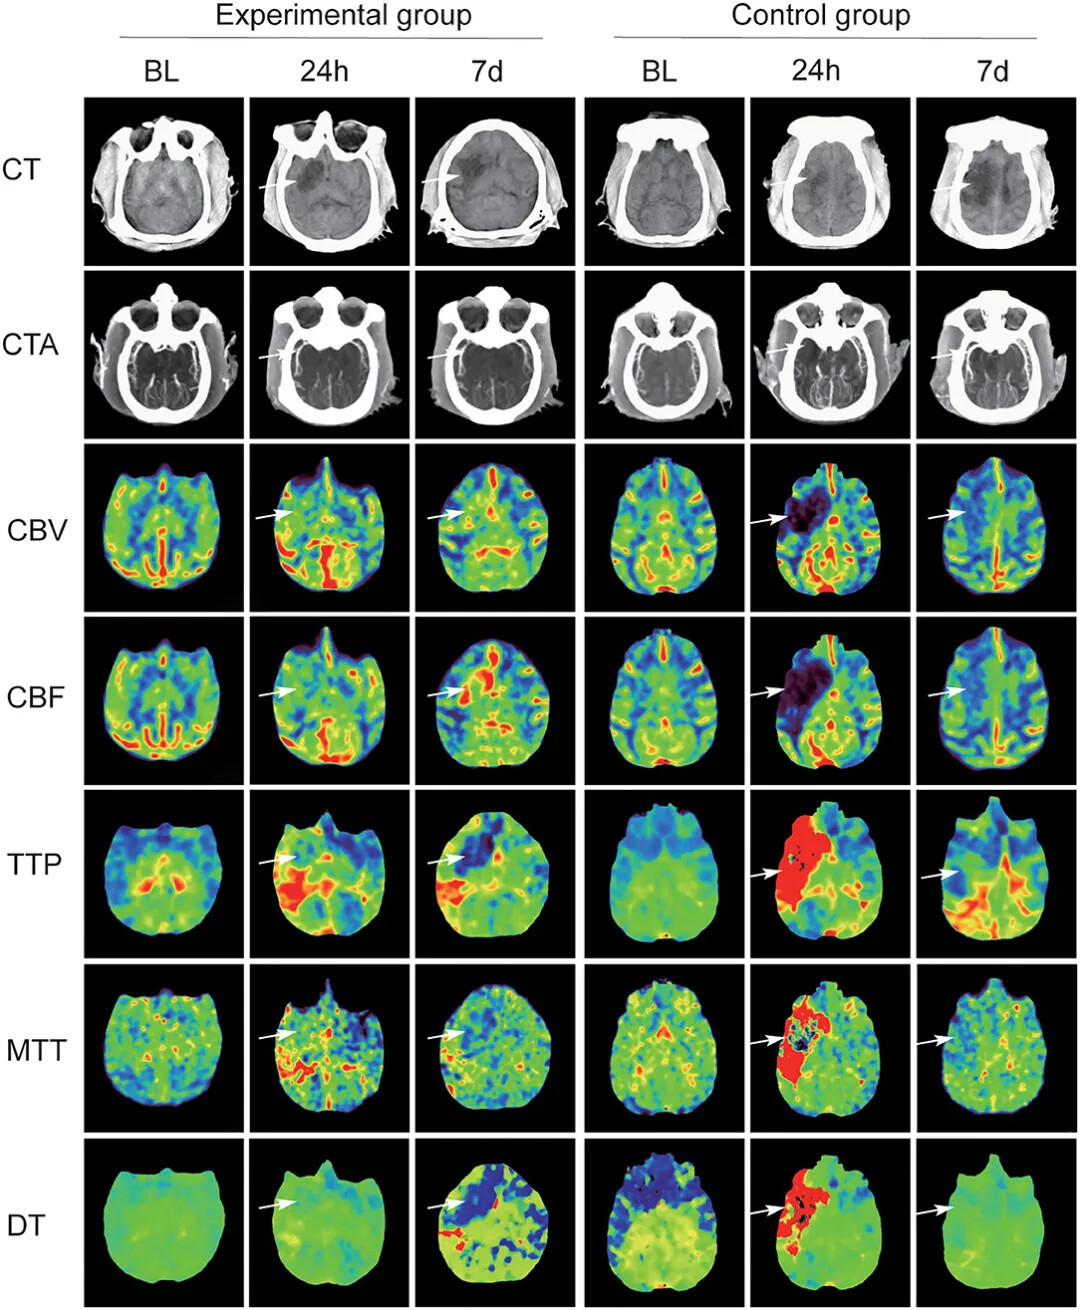

两组MCAO模型的CT扫描图像对比总结。在实验组中,术后24小时和第7天进行的CT血管造影(CTA)扫描显示,MCA及其远端分支再通,但实验组的MCA未显影。两组在CT灌注(CTP)扫描中的差异显著(白色箭头)。

目前,浦灵生物已建立的成熟食蟹猴MCAO模型,相关数据已发表于Frontiers in Neurology杂志,并借助该动物模型成功助推了多款新药的临床前药效评价。- 血管再通情况:使用CTA、MRA和CTP成像评估血管再通效果。

- 脑组织的缺血变化:通过MRI和DWI序列观察急性脑缺血区域。